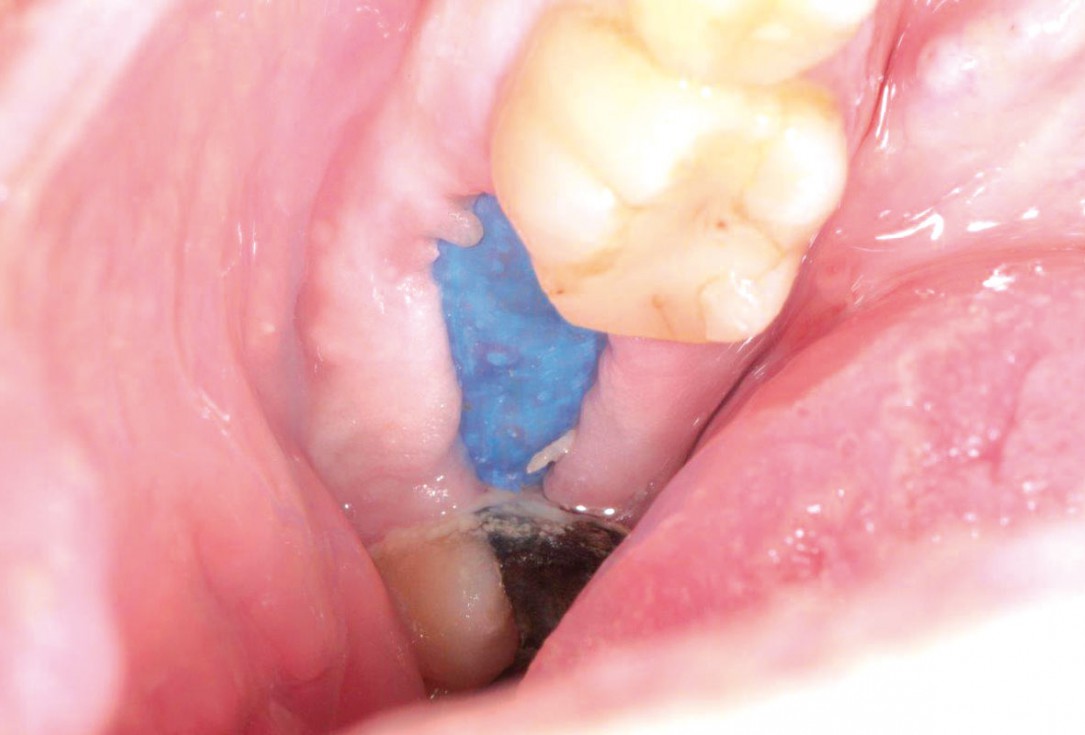

botiss cerabone® & collprotect® membrane for GBR - Clinical case by Dr. V. Kalenchuk

Clinical situation with narrow alveolar ridge in the lower jaw